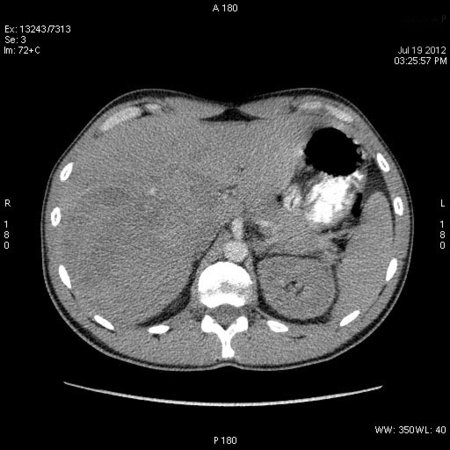

КТ через день

После КТ хирурги заказали дренирование "абсцесса".

Выполнена диагностическая пункция из 4х участков, получена только кровь.